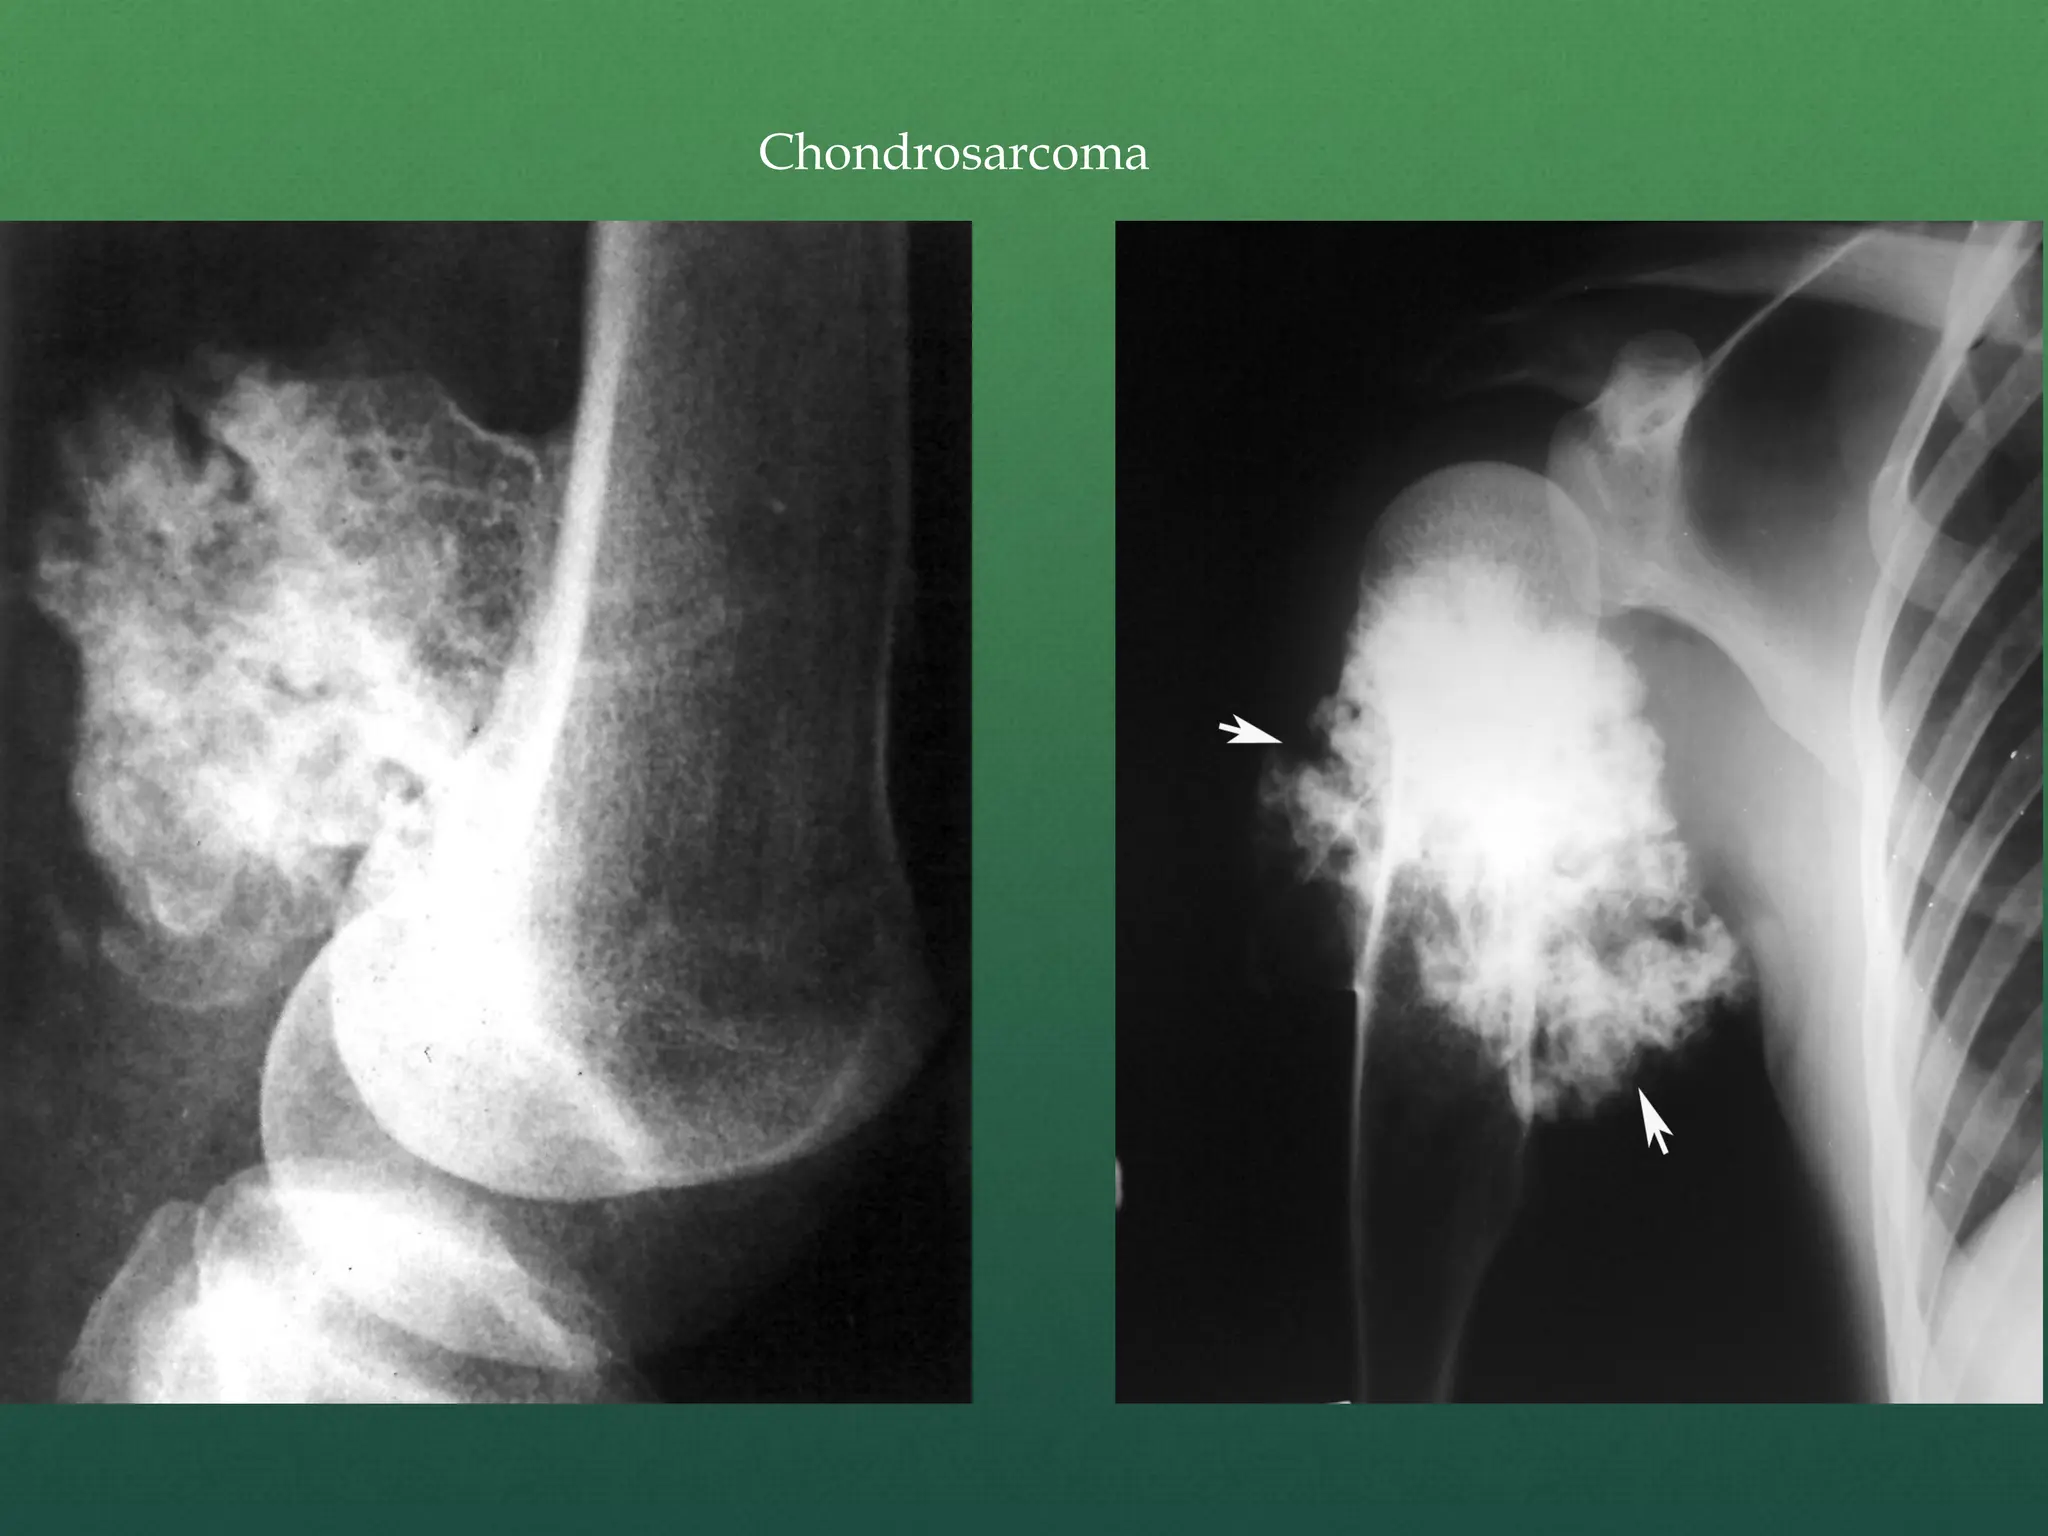

 X – ray –

Chondrosarcoma is a fusiform, lucent defect with

scalloping of the inner cortex and periosteal reaction.

Extension into the soft tissue may be present as well as

punctate or stippled calcification of the cartilage

matrix.

Chondrosarcoma